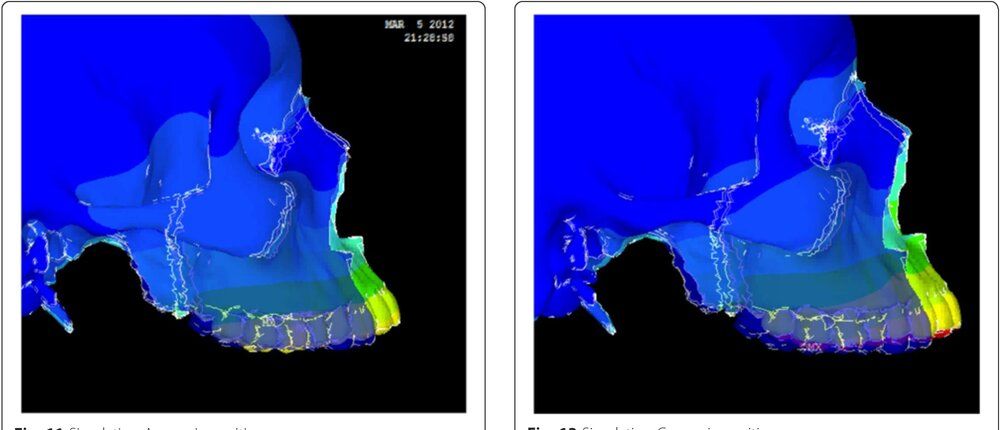

Now look at the displacement if the micro-implant was placed in a better location with a pulling angle of -15 degrees (Simulation C, picture on the right on the second picture) :

look at how signifiant is the forward displacement, look at how the maxilla rotate ccw.